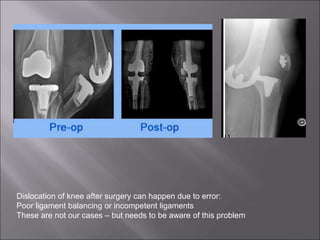

Dislocation of knee after surgery can happen due to error:

Poor ligament balancing or incompetent ligaments

These are not our cases – but needs to be aware of this problem